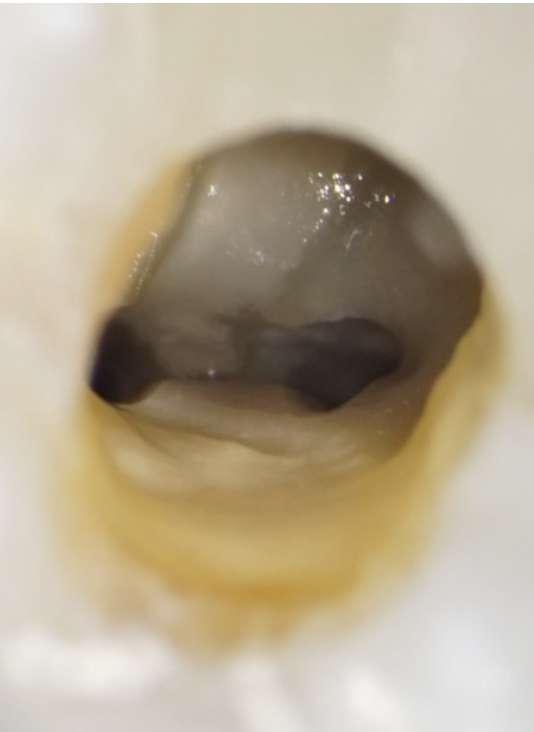

Die endodontische Behandlung fand in einer Sitzung statt. Nach Anästhesie und Anlegen des Kofferdams erfolgte die Entfernung der provisorischen Füllung und die initiale intrakoronale Diagnostik. Mittels Microopener konnte ein mesiobukkaler, mesiolingualer, distobukkaler und distolingualer Wurzelkanal sondiert werden. Die Ausarbeitung der primären Zugangskavität zur besseren Zugänglichkeit der Kanäle erfolgte mit Langschaftrosenbohrern. Anhand des präoperativen diagnostischen Röntgenbilds konnte die Länge der Wurzelkanäle vorläufig näherungsweise bestimmt werden. Die Kanäle wurden im weiteren Therapieverlauf kontinuierlich mit 6% NaOCl gespült. Nach Ausarbeitung der Zugangskavität folgte die koronale Erweiterung der Wurzelkanäle mit EdgeEndo X7 Feilen der Größe 17.06. Die elektrometrische Bestimmung der Kanallänge mithilfe eines Morita Root ZX Mini Apex Locators wurde mit C-Piloten der Größe 8-10 durchgeführt. Nach Festlegung der Arbeitslänge wurde der

Gleitpfad rotierend mit EdgeFile X7 der Größe 17.04 und 25.04 erweitert und final bis auf 30.04 aufbereitet (Abbildung 2).

Abbildung 2: Blick auf das mesiale Kanalsystem nach Präparation